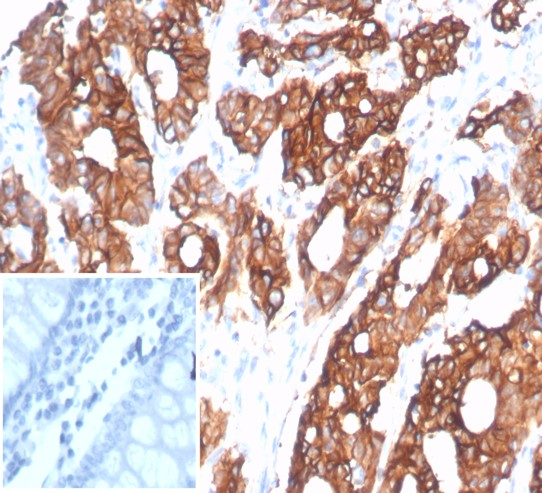

| Applications: | IHC |

Recombinant Monoclonal Antibody

| Reactivity: | Human |

| Details: | Rabbit IgG Kappa Monoclonal Clone #S100A14/9077R |

| Applications: | IHC |

![Immunohistochemistry-Paraffin: S100 calcium binding protein A14 Antibody (S100A14/9077R) - Azide and BSA Free [NBP3-24305] -](https://resources.bio-techne.com/images/products/nbp3-24305_rb-s100a14-mab-s100a14-9077r-azide-bsa-free-1312202316331820.jpg)

![Immunohistochemistry-Paraffin: S100 calcium binding protein A14 Antibody (S100A14/9077R) [NBP3-23639] - S100 calcium binding protein A14 Antibody (S100A14/9077R)](https://resources.bio-techne.com/images/products/nbp3-23639_rabbit-s100-calcium-binding-protein-a14-mab-s100a14-9077r-1312202311502947.jpg)